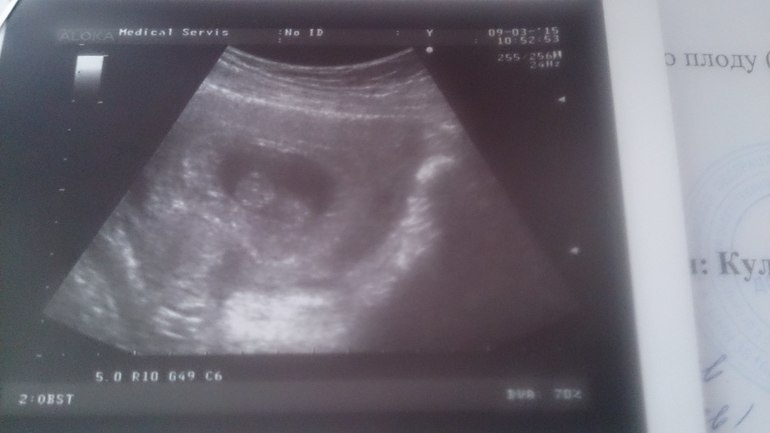

Результаты: УЗИ, КТГ, доплера, скринингаСегодня была на узи, акушерский срок 10 недель 1 день, от последнего узи 9 недель 6 дней, а сегодня измерили ктр 27 мм и какого то хрена простите, поставили ровно 8 недель. Узист другой. Я не понимаю, по чему мне уменьшили срок ведь норма моего ктр для 9-10 недель. Вот так мы выглядим, неужели тянем только на 8?!